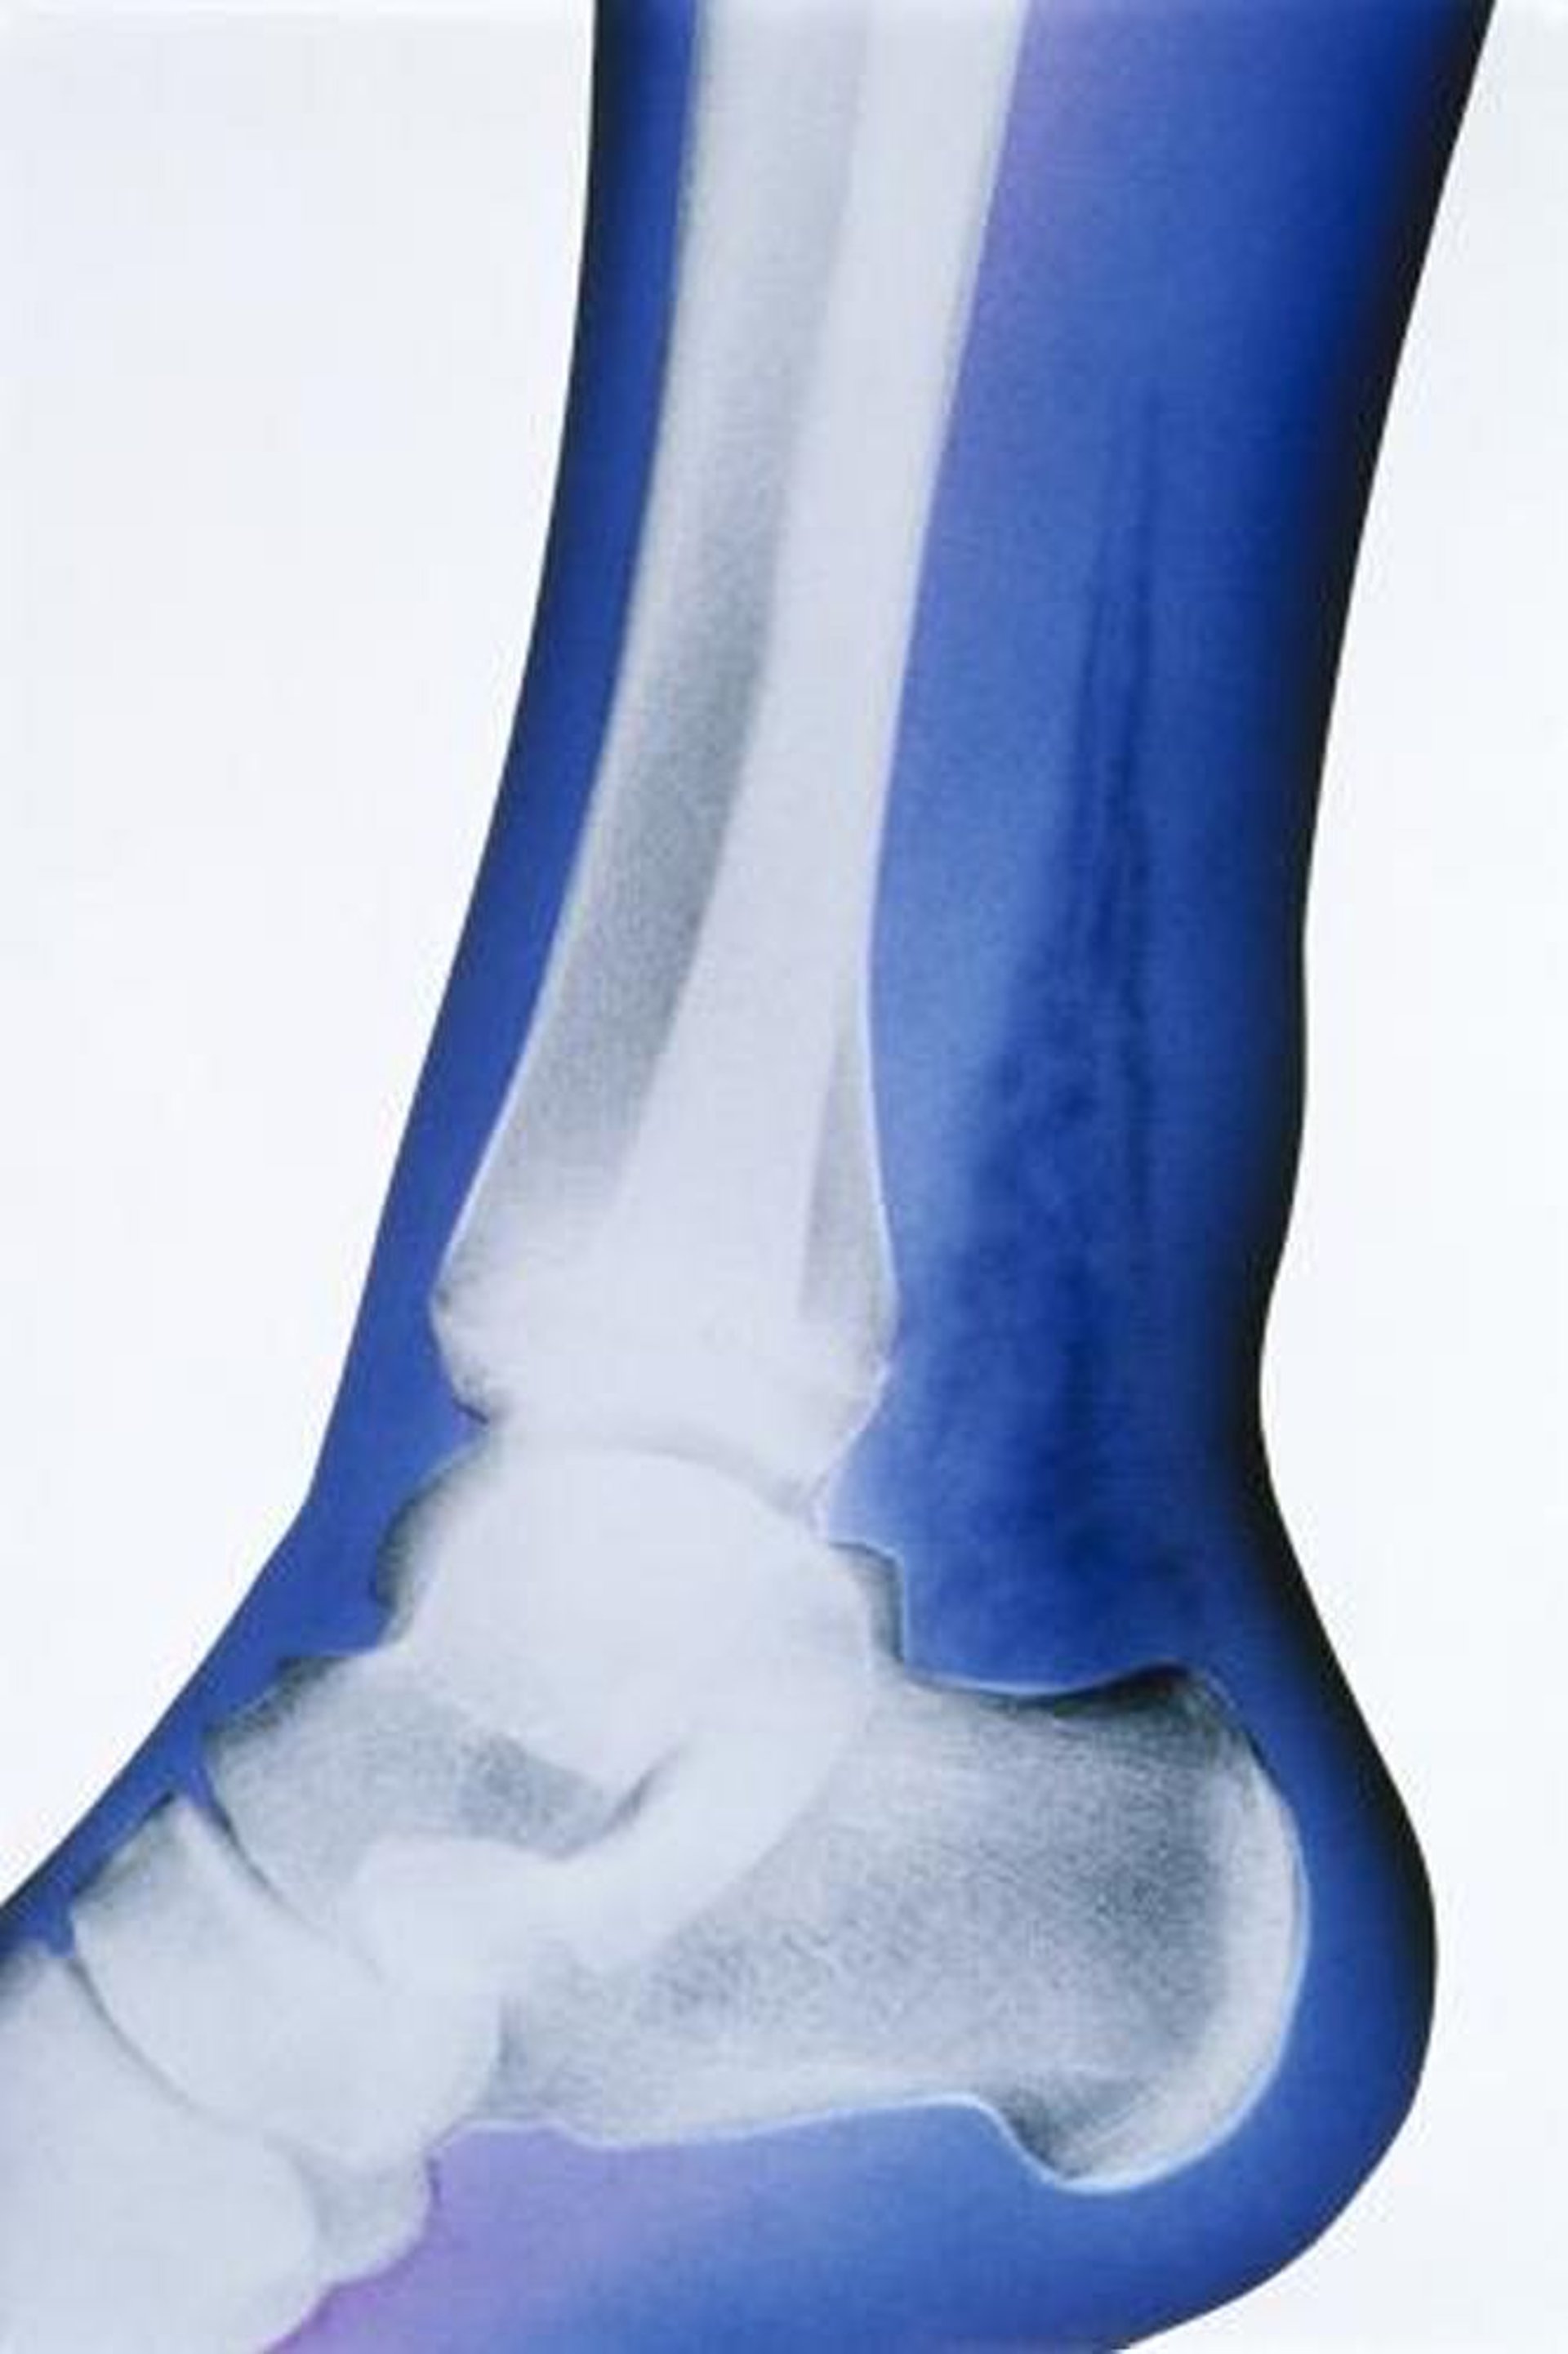

壊死性皮下組織感染症(X線)

この人工的に着色したX線写真では,軟部組織内のガスが目立った所見であり,その存在は踵骨の上方かつ脛骨および腓骨の後方に位置する放射線透過性の高い領域によって示されている。